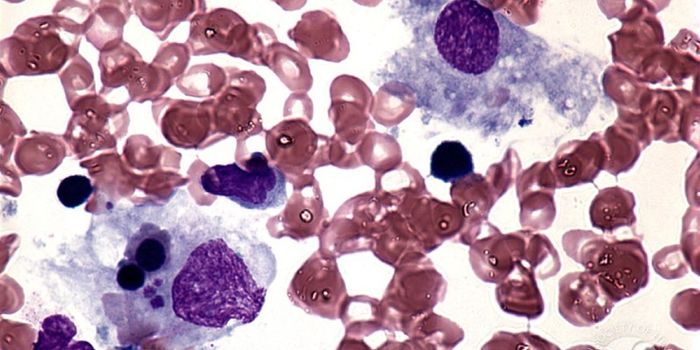

FEB 12, 2016ImmunologyAcute lymphoblastic leukemia (ALL) and non-Hodgkin’s Lymphoma (NHL) affect 75,000 and 72,000 people each year in t ...

MAR 18, 2015Immunology

After a chance observation in the lab, researchers found a method that can force dangerous leukemia cells in the l ... -